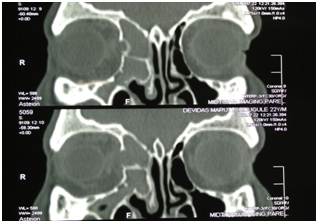

A 22years old male presented with bilateral blocked nose sensation (right>left) since 7-8months, persistent frontal headache. History of right sided facial heaviness and pain with right periorbital swelling. No history of trauma, clear fluid discharge from nose. No history of recurrent episodes of upper respiratory tract infections/ recurrent episodes of sneezing/running nose or any previous trauma. On examination, anterior rhinoscopy showed mucopurulent discharge and crusting, nasal endoscopy showed bilateral inferior turbinate hypertrophy, mucosa was normal. CT scans of paranasal sinuses showed large homogenous expansile cystic lesion obstructing the right frontal sinus drainage. Another homogenous mass was noted in extending to the right ethmoid sinus suggesting the possible diagnosis of two separate frontal and ethmoid mucoceles with pansinusitis and right sided proptosis (Figure 1-3).

Figure 1 & 2 CT scans showing homogenous masses in the right frontal and ethmoid sinuses.

Figure 3 CT scan suggestive of right side proptosis.